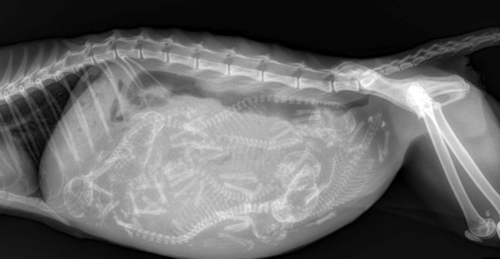

Radiology (X-ray) is a non-invasive diagnostic tool used to assist in the diagnosis of many concerning conditions and traumas.

• Pregnacy Verification and Fetal Count